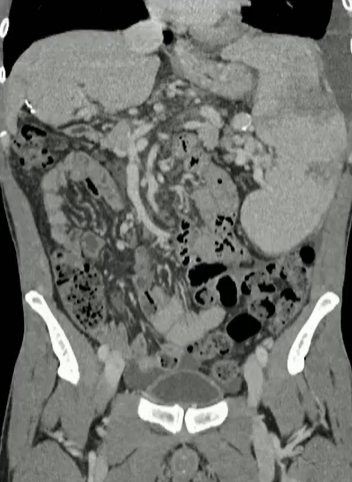

50岁 男性, 外科医生,25 年前的 PVT;目前胸水,工作繁重,生活受限,每周一次胸水引流,由于慢性肺静脉血栓形成而进行的移植手术

步骤: 鉴于慢性血栓形成的复杂性: 一种经脾脏途径的门静脉再通术(PVR)。 随后是经颈静脉肝内门体分流术 。

结果:术后影像学检查显示门静脉和脾静脉的血流情况有所改善,且残留血栓极少。

通过经颈静脉肝内门体分流术(TIPS)治疗慢性门静脉血栓时所涉及的技术复杂性和决策难题,尤其是在标准方法因血栓程度过重而无法实施的情况下更是如此。 采用脾经脏穿刺术治疗门静脉高压症的方法证明能够有效克服这些难题,从而成功实施了经颈静脉肝内门体分流术(TIPS)。 PVR-TIPS 作为一线治疗方案:PVR-TIPS 为慢性门静脉血栓的治疗提供了一种技术上可行的解决方案,克服了标准 TIPS 安装所面临的难题。 持久效果:该干预措施不仅恢复了门静脉的血流,而且在后续随访中还显示出持续的通畅性以及血栓的完全消散。